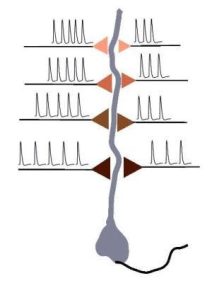

The brain learns basically by shifting between different strengths of its synapses, as a response to different stimuli – that much is clear. However, recently, a team of UCLA scientists have shattered the common belief about the mechanism of learning, showing that the brain learns rhythmically, and that there is an optimal ‘rhythm’, or frequency, […]